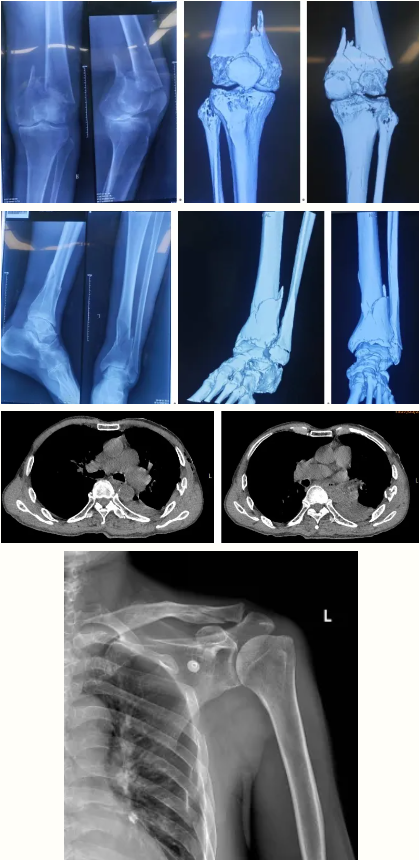

术前影像:

王大爷左侧血气胸病情严重,左肺扩张受限,胸廓活动受阻,出现呼吸浅促、胸闷气短等症状。此外,双下肢多处骨折带来的剧烈疼痛,进一步限制呼吸,导致肺泡通气不足。加之多发骨折伴随失血,血红蛋白持续偏低,呼吸与循环系统面临“双重危机”。

患者病情平稳后,术前再次完善血管超声、X线、CT及MRI等检查,并由骨科牵头,联合麻醉手术科、心胸外科、重症医学科、呼吸科、心内科、影像医学科、输血科进行多学科会诊评估,全面评估手术风险,制定详尽的分阶段手术方案,确保患者以最佳状态接受手术治疗。

术后影像: